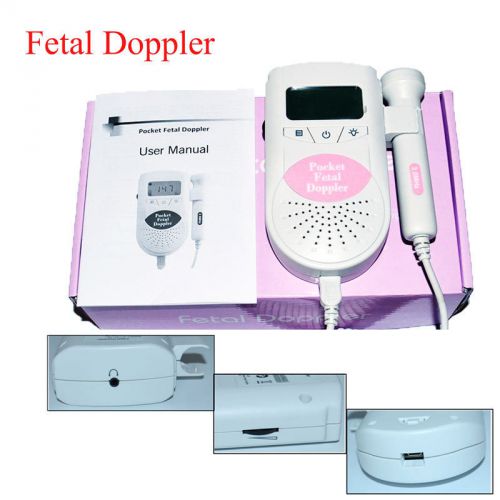

Similar products from Pre-Birth Heart Monitors

LCD Prenatal Pocket Fetal Doppler Approved Baby Heart Beat Monitor Orange+Gel

USA Shipment! FDA Fetal Doppler, Baby heart Monitor,3MHz probe with Free GeL

USA SHIPPING Ultrasound Prenatal Fetal Doppler LCD unburn Baby Heart FHR BB PINK

Sonoline heart beat baby monitor white & pink

Sonoline B Fetal heart doppler Hear your baby's heartbeat Contec + accessory lot

Blue Jumper Fetal Doppler Baby Heart Sound Pregnant monitor FDA CE + Earphone

Ultrasound Prenatal Detector Pocket Fetal Doppler 3.0 Mhz Probe FDA CE Free P&P